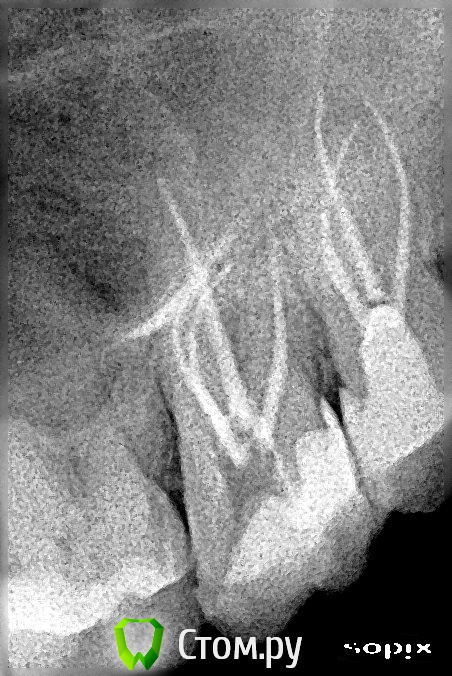

Miria Опубликовано 26 мая, 2014 Поделиться Опубликовано 26 мая, 2014 Здравствуйте!В начале марта 2014 г. лечила 28 (периодонтит острый серозный, зуб болел с декабря 2013 г.) под анестезией, лекарство и временная пломба на 1-м приеме, пломбировка 3-х каналов термафил и постоянная пломба на 2-м приеме (через 8 дней). После лечения болей не было.1 апреля лечила 27 (пульпит хронический в стадии обострения фиброзный, зуб болел с декабря 2013 г.) под анестезией, пломбировка 4-х каналов термафил на 1-м приеме, постоянная пломба на 2-м приеме (через 9 дней). После лечения зуб болел 4 дня, сразу появилось: тепло в области левых скулы и виска; распирание всего зуба, которое усилилось далее; подергивание нерва глубоко в левой щеке ближе к носу. Через 10 дней началось онемение в области левых скулы и глаза, позднее резко ухудшалось зрение. Зуб был болезненный при задевании, ломота, неприятный вкус слюны около 27.25 апреля был распломбирован один канал (небный) и пройден до верхушки, оставлено лекарство, временная пломба (по плану на 24 дня). Прошло онемение скулы и глаза, восстановилось зрение. Распирание, ломота, болезненность, тепло в виске и скуле, подергивание нерва в щеке продолжались и случился сильный приступ боли через 7 дней.3 мая снята временная пломба, лекарство, временная пломба. Пропила назначенный Рулид 5 дней по 1 таблетке 2 раза в день. Исчез неприятный вкус слюны. Распирание, ломота, болезненность, тепло в виске и скуле, подергивание нерва в щеке продолжались.7 мая снята временная пломба, частично распломбирован еще один канал (который по снимку ближе к 26), лекарство, временная пломба. Подергивание нерва в щеке и тепло немного уменьшились. Распирание, ломота, болезненность продолжались.19 мая (24-й день после распломбировки небного канала) снята временная пломба, немного распломбирован еще один канал (который по снимку ближе к 28), запломбирован небный канал, временная пломба.Распирание, ломота, болезненность при задевании, покалывание в щеке, постоянное подергивание нерва в щеке (ближе к носу) продолжаются. Не совсем прошла боль в виске. На снимке выведена пломбировка за апекс.Очень переживаю за зуб. Вопросов много и срочные, может, что еще скажете.1. Почему может болеть зуб 27?2. Какова методика дальнейшего лечения 27?3. Нужно ли убирать выведенный материал, если он дает такую реакцию? Или со временем боль может пройти (такая боль продолжается с первого приема лечения с 01.04.2014, терпению давно предел)?4. Может ли получиться убрать выведенный материал за верхушками через распломбированные каналы или как? (По-моему хирургически просто не добраться) И если вновь распломбировывать – то распломбировывать надо сразу все каналы (небный канал запломбирован два раза)?5. Повторное эндодонтическое лечение намного хуже для зуба или как оно влияет на дальнейшее функционирование зуба?Спасибо огромное за Ваши время и ответ, который очень жду! 1 Ссылка на комментарий

Miria Опубликовано 12 июня, 2014 Автор Поделиться Опубликовано 12 июня, 2014 Здравствуйте, добавляю снимки. Ссылка на комментарий